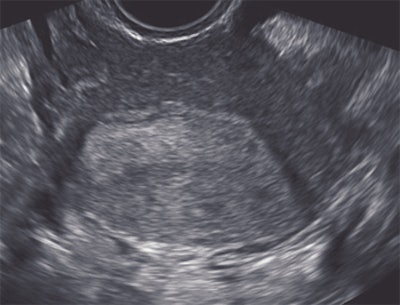

| A 31-year-old woman who presented with infertility. Above, transverse view through uterus shows no abnormality. Below, reconstructed coronal view of uterine cavity shows arcuate uterus. Benacerraf B, Shipp T, Bromely B, "Which Patients Benefit from a 3D Reconstructed Coronal View of the Uterus Added to Standard Routine 2D Pelvic Sonography?" (AJR 2008; 190:626-629). |